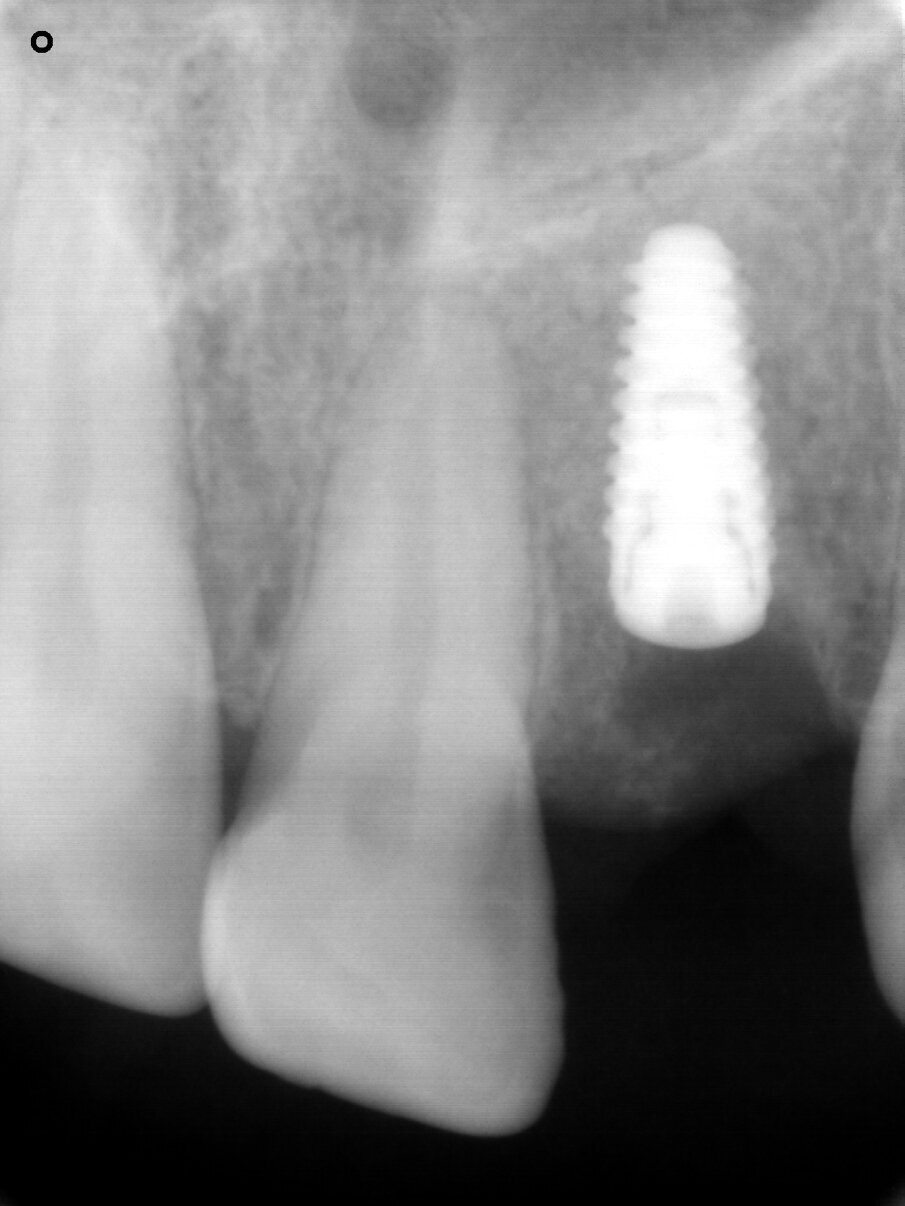

A 39-year-old male patient presented to our clinic with a fractured tooth #21 (Figs. 16 & 17). The CBCT scan showed an unfavourable root–crown ratio for tooth #21 (Fig. 18), which was an indication for extraction.

The socket shield technique was planned for this case. Vertical root sectioning was done, removing the palatal part of the root and leaving the facial section intact. Another CBCT scan was taken, and it showed the guide pin in place (Fig. 19). The implant was placed without flap elevation (Fig. 20), and bone substitute was placed to fill the gap (Fig. 21). A screw-retained provisional restoration was placed immediately after implant placement to guide the periodontal tissue healing (Fig. 23). Four months after the procedure, the definitive screw-retained restoration was placed, and very satisfying aesthetic and functional results were evident (Fig. 24).

Fig. 19: CBCT scan showing the facial root section and the guide pin in place.

Fig. 20: Vertical sectioning of the root and atraumatic extraction of the palatal half in the socket shield technique and placement of the implant into site #21.